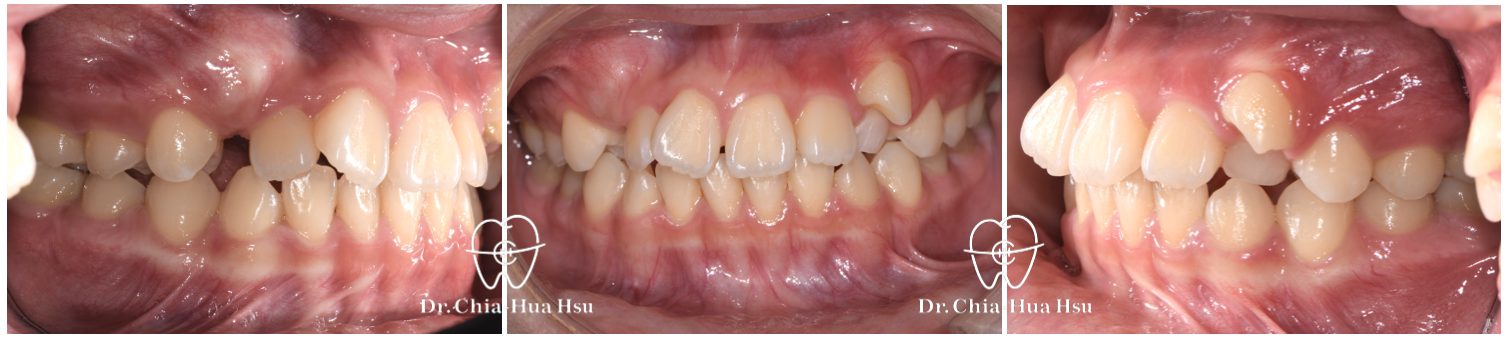

治療前

治療後